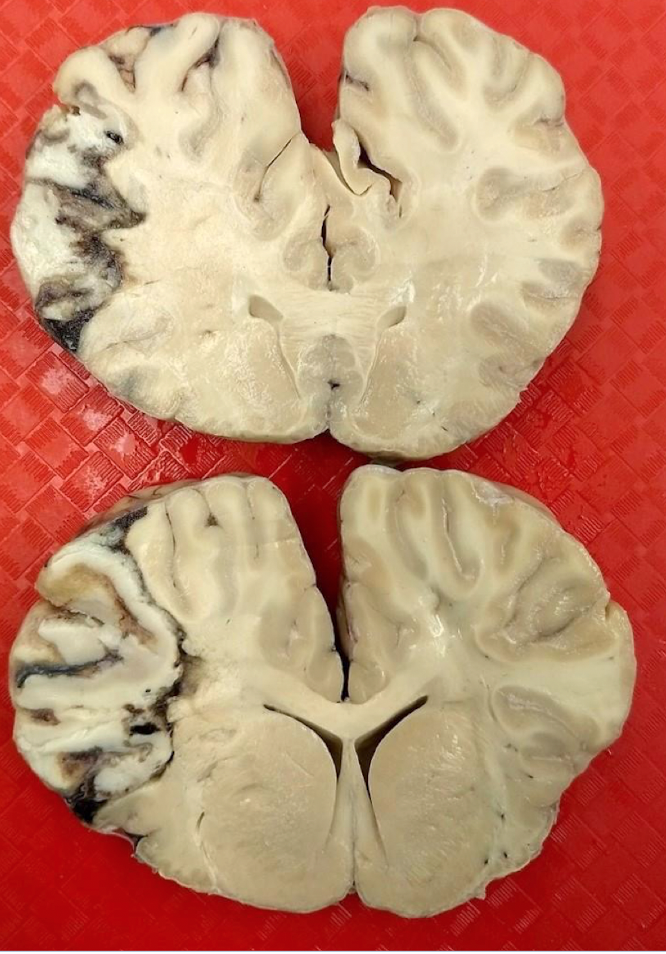

Description: There is a sharply demarcated zone of the left cerebral hemisphere that is cream-colored centrally with a dark red-brown rim. This area measures approximately 3 X 4 cm on the cut surface of the more caudal of the two sections, and approximately 1.5 X 4 cm on the more rostral of the sections.

Morphologic diagnosis: Severe locally extensive acute to subacute infarct of the cerebral hemisphere.

The brain has high oxygen and nutrient requirements and poor collateral circulation.

Infarcts lead to coagulative necrosis in most tissues, although it often results in liquefactive necrosis in the brain.

A cerebrovascular accident, or stroke (more common in humans than in animals)